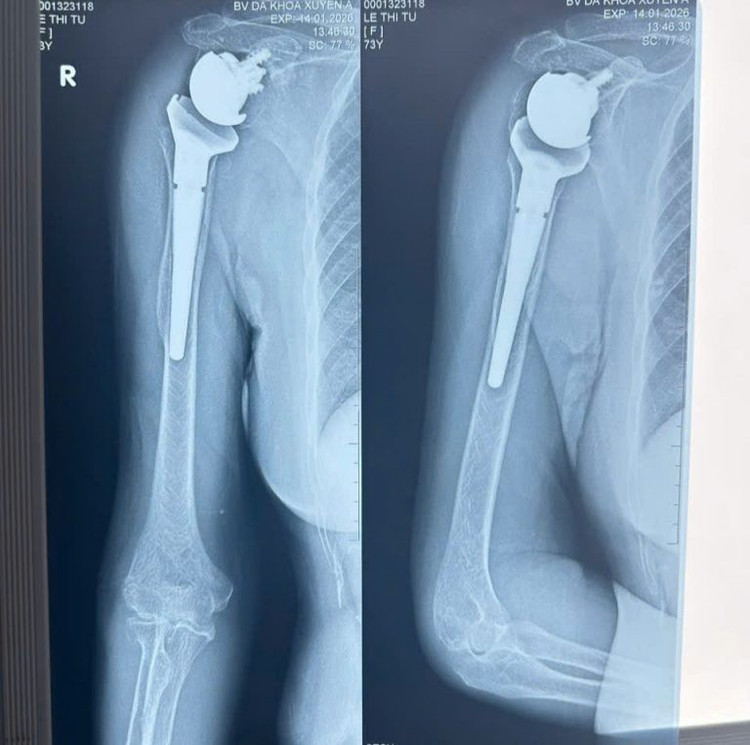

Kết quả chụp X-quang cho thấy bệnh nhân bị gãy nát đầu trên xương cánh tay bên phải thành nhiều mảnh nhỏ, các mảnh xương gãy rời rạc, chỏm xương cánh tay bị trật hoàn toàn khỏi ổ chảo xương bả vai, gây tổn thương nghiêm trọng cấu trúc khớp vai.

Hình ảnh X-quang trước và sau khi thực hiện phẫu thuật thay khớp vai đảo nghịch - Ảnh BVCC

Sau gần 2 giờ thực hiện, ca phẫu thuật thành công tốt đẹp, khớp vai nhân tạo được đặt đúng vị trí giải phẫu, cố định vững chắc. Ngay sau phẫu thuật, người bệnh cũng giảm đau rõ rệt.